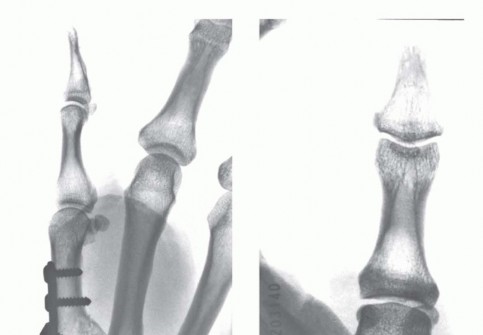

For a large fragment Bennett fracture, the shaft is reduced to the volar-ulnar fragment using a pointed reduction clamp. Provisional fixation is achieved with a K-wire. A 1.5mm or 2.0mm lag screw is then placed perpendicular to the fracture plane. The near cortex must be overdrilled (gliding hole) and the far cortex underdrilled (thread hole) to achieve true interfragmentary compression. The screw head should be countersunk to prevent hardware prominence beneath the thenar muscles.

Fixation Strategies for Rolando and Comminuted Patterns

Rolando fractures present a significantly higher degree of complexity. The classical Y or T pattern often precludes simple lag screw fixation. In these instances, mini-fragment plating is the gold standard. T-plates or specialized condylar plates are contoured to fit the complex geometry of the metacarpal base. The articular fragments are first reduced and provisionally pinned, essentially converting the complex intra-articular fracture into a simpler two-part extra-articular fracture. The plate is then applied to buttress the articular fragments and bridge the metaphyseal comminution to the diaphysis.